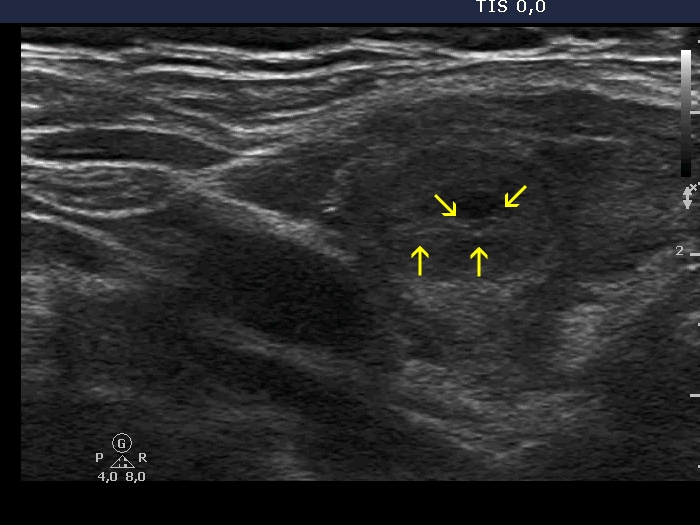

Lymphocytic thyroiditis - case 1442 (ultrasonographic picture 3b)

Right lobe, another longitudinal view. Note some pale echogenic lines and granules which had no relevance at the time of the actual investigation.